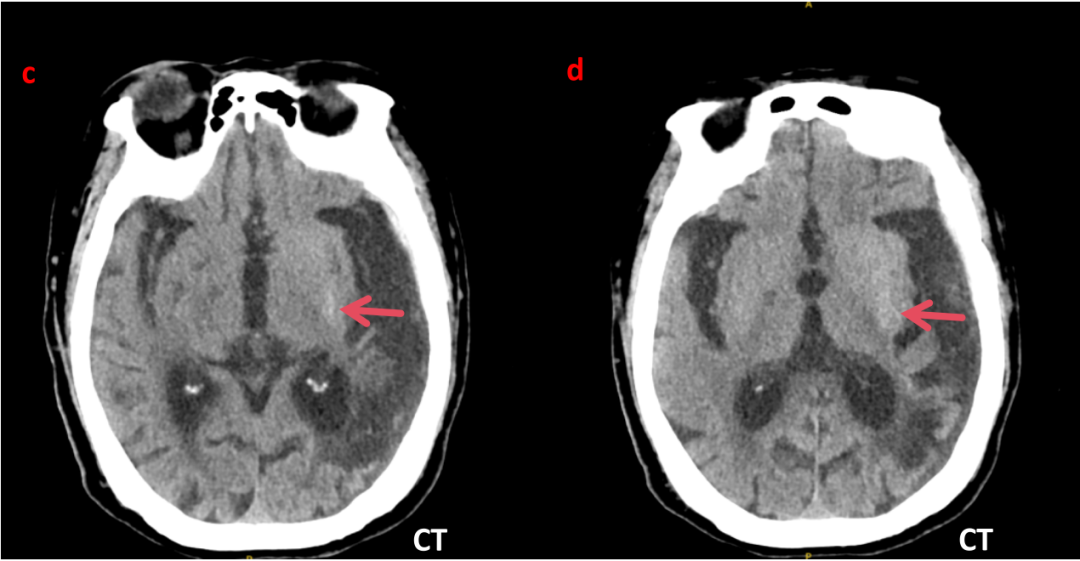

颅脑CT平扫

:左侧颞枕叶大片软化灶;左侧颞顶部颅板下见带状高密度影(提示左侧颞顶部硬膜下血肿);左侧基底节区小片状略高密度影;两侧脑室旁、基底节区腔梗。(图c、d)

c、d 图为患者入院4天后(2025-10-27跌倒坠床)完善头颅CT图像,提示左侧基底节区高密度影,CT值40HU,无水肿

及占位效应,结合MR,此处高密度影不考脑出血

相关。

(4)微出血学说:Nath等尸检发现HC⁃NH患者病灶处微量出血,但其出血不同于一般脑出血,血肿局限于豆状核及壳核,不压迫内囊及邻近结构,无水肿及占位效应,且MRI不符合脑出血时间演变规律。

高血糖可导致多种神经系统损害,当并发运动障碍时,多表现为偏身舞蹈症,当急性发作时典型的影像表现为对侧纹状体MRI T1WI 高信号,T2WI 则为多变信号,边界清晰,无水肿现象,CT 平扫高密度为该并发症的特异改变。虽然糖尿病纹状体病影像表现具有明显特征性,但当表现出明显 T1WI 高信号、T2WI 低信号及 CT 高密度时,仍需要与出血相鉴别。急性脑内出血周围可见明显水肿信号并且当豆状核、尾状核头均受累时内囊会受累,且 DWI 可明显弥散受限,1~2 周复查糖尿病纹状体病影像改变不明显但是出血改变明显,这些均是重要鉴别点。 DS 患者影像学检查具有特征性表现,患肢对侧纹状体,主要是尾状核头和壳核,发病初期 CT 表现为高密度灶,信号不均匀,急性期呈片状改变,MRI 上 TWI 基底节区尤其是壳核呈高信号,在基底节其他结构性或代谢性损害中未见到这种影像学改变。此影像学表现的解释

本例患者中年女性,本次表现为突发右上肢及右侧面部不自主运动,平素糖尿病管理较差,入院血糖水平高达28.31 mmol/L,呈非酮症非高渗状态,MRI在左侧(舞蹈运动障碍肢体对侧)基底节区出现特征性T1WI 高信号表现,头颅CT左侧基底节区片状高密度影,血糖控制良好后症状完全消失,符合DS诊断的特征性改变。患者无肝病史,肝功能、甲功能、血钙磷、铜蓝蛋白无异常,颅内无钙化灶,查体无K-F环,排除亨廷顿舞蹈症、肝豆状核变性、基底节钙化、甲状旁腺功能减退、风湿免疫相关疾病等;患者无发热,无毒物及一氧化碳中毒,无免疫系统相关疾病等,排除药物、中毒、免疫、细菌等相关获得性舞蹈症。患者糖尿病纹状体病诊断成立。但该患者需后续进行随访,如颅脑影像学检查提示右侧基底节区高密度影缩小或消退,更支持DS诊断。